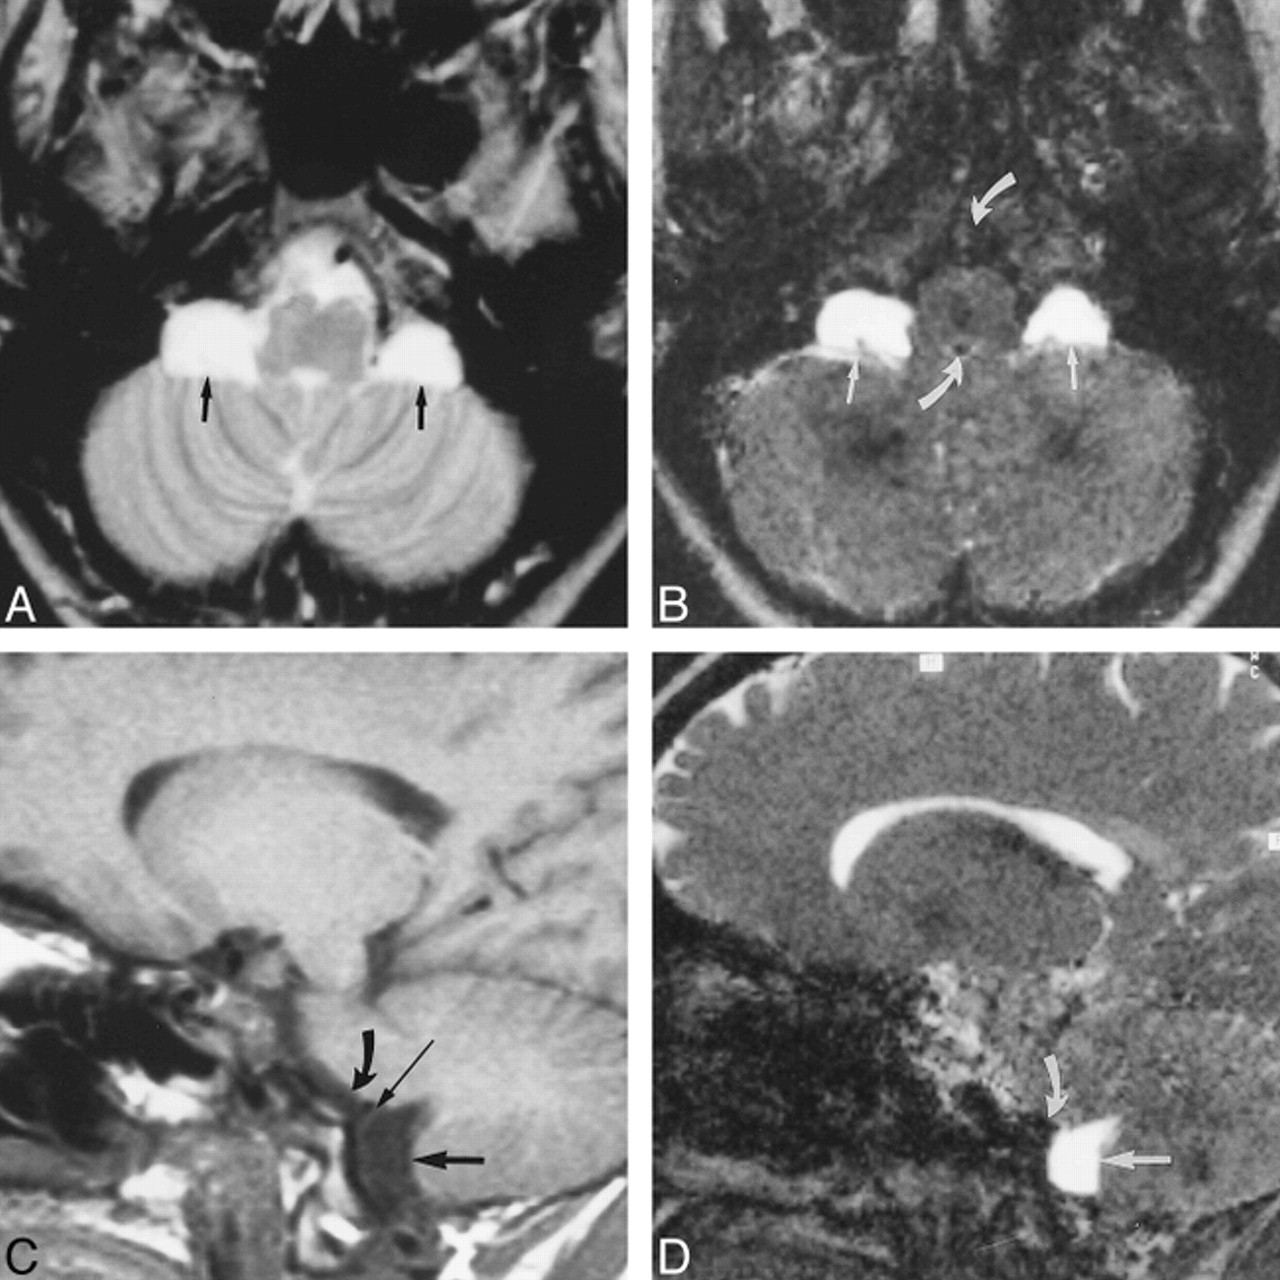

23-year-old man with a left-sided temporal arachnoid cyst, suffering from occasional headaches.

A, Transverse T2-weighted SE image (2000/80/1) shows a hyperintense left temporal arachnoid cyst.

B, Coronal PSIF image (20/25/1) depicts distinct signal reduction (arrow) arising from the basal cisterns, indicating probable communication.

C, CT cisternogram (3-hour delay) shows slight contrast enhancement within the cyst, confirming slow communication. The contrast enhancement was confirmed by measuring a clear increase of intracystic HU. The site of communication was not detectable on the CT cisternogram owing to proposed valve mechanism with slow communication.

6-year-old girl with a system of temporal, supra- and parasellar, and paracerebellar arachnoid cysts.

A, Transverse T2-weighted SE image (2000/80/1) shows a right and small left temporal, suprasellar, and paracerebellar cysts. Note hamartoma of the tuber cinereum (arrow) anterior to the rotated brain stem.

B, Parasagittal PSIF image (20/25/1) shows some evidence of communication between the parasellar and paracerebellar cysts in the form of a continuous flow void (arrow).

C, CT cisternogram shows contrast enhancement with layering in the parasellar and paracerebellar cysts (arrows), providing further evidence of communication. Layering was caused by the patient's prolonged supine position.